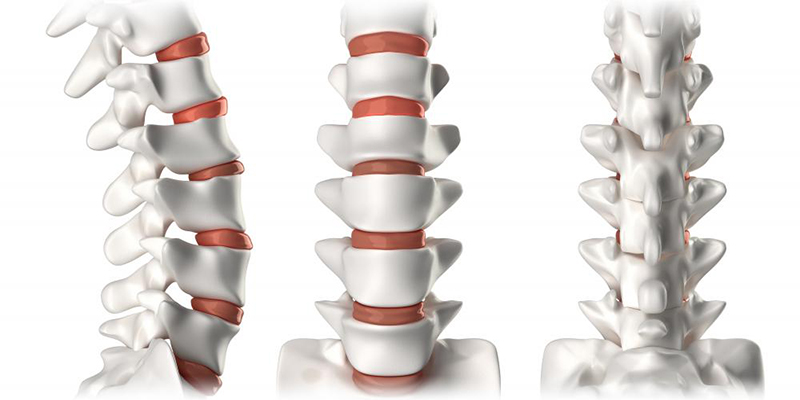

- بالش: استفاده از بالش مناسب نیز اهمیت دارد. بالش نباید زیاد بالا یا پایین باشد، بلکه باید سر و گردن را در خط مستقیم با ستون فقرات قرار دهد. استفاده از بالش مناسب کمک میکند تا مراقبت درستی از ستون فقرات صورت بگیرد.

نوع نشستن و ایستادن در دیسک کمر باید به گونهای باشد که قوسهای طبیعی ستون فقرات حفظ شود. همچنین، نباید قوز کرد و بهتر است از صندلیهای دارای ارتفاع مناسب و پشتی که قوس محافظ کمر دارند، استفاده کنید. استفاده از این نوع صندلی پشتیبانی مناسبی از کمر شما انجام میدهد.